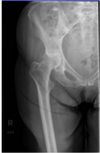

For this proximal AP femur what corrections should be made? A - Bring centering proximal 2 inches and internally rotate leg B - Externally rotate the leg to visualize the lesser trochanter in profile C - Bring centering distal 2 inches and internally rotate leg D - Internally rotate the leg to visualize the lesser trochanter in profile

C - Bring centering distal 2 inches and internally rotate leg In the AP proximal femur sample provided, the centering is too high. When imaging the femur, it is important to have precise centering to avoid anatomy cutoff. The top of the IR should be placed at the ASIS, and there should be 1-2 inches of overlap between the proximal and distal AP images taken. Centering 2 inches distal would be ideal. Internal rotation of 15-25° is needed for the AP femur, to place the femoral neck parallel to the IR and to visualize the greater trochanter in profile.